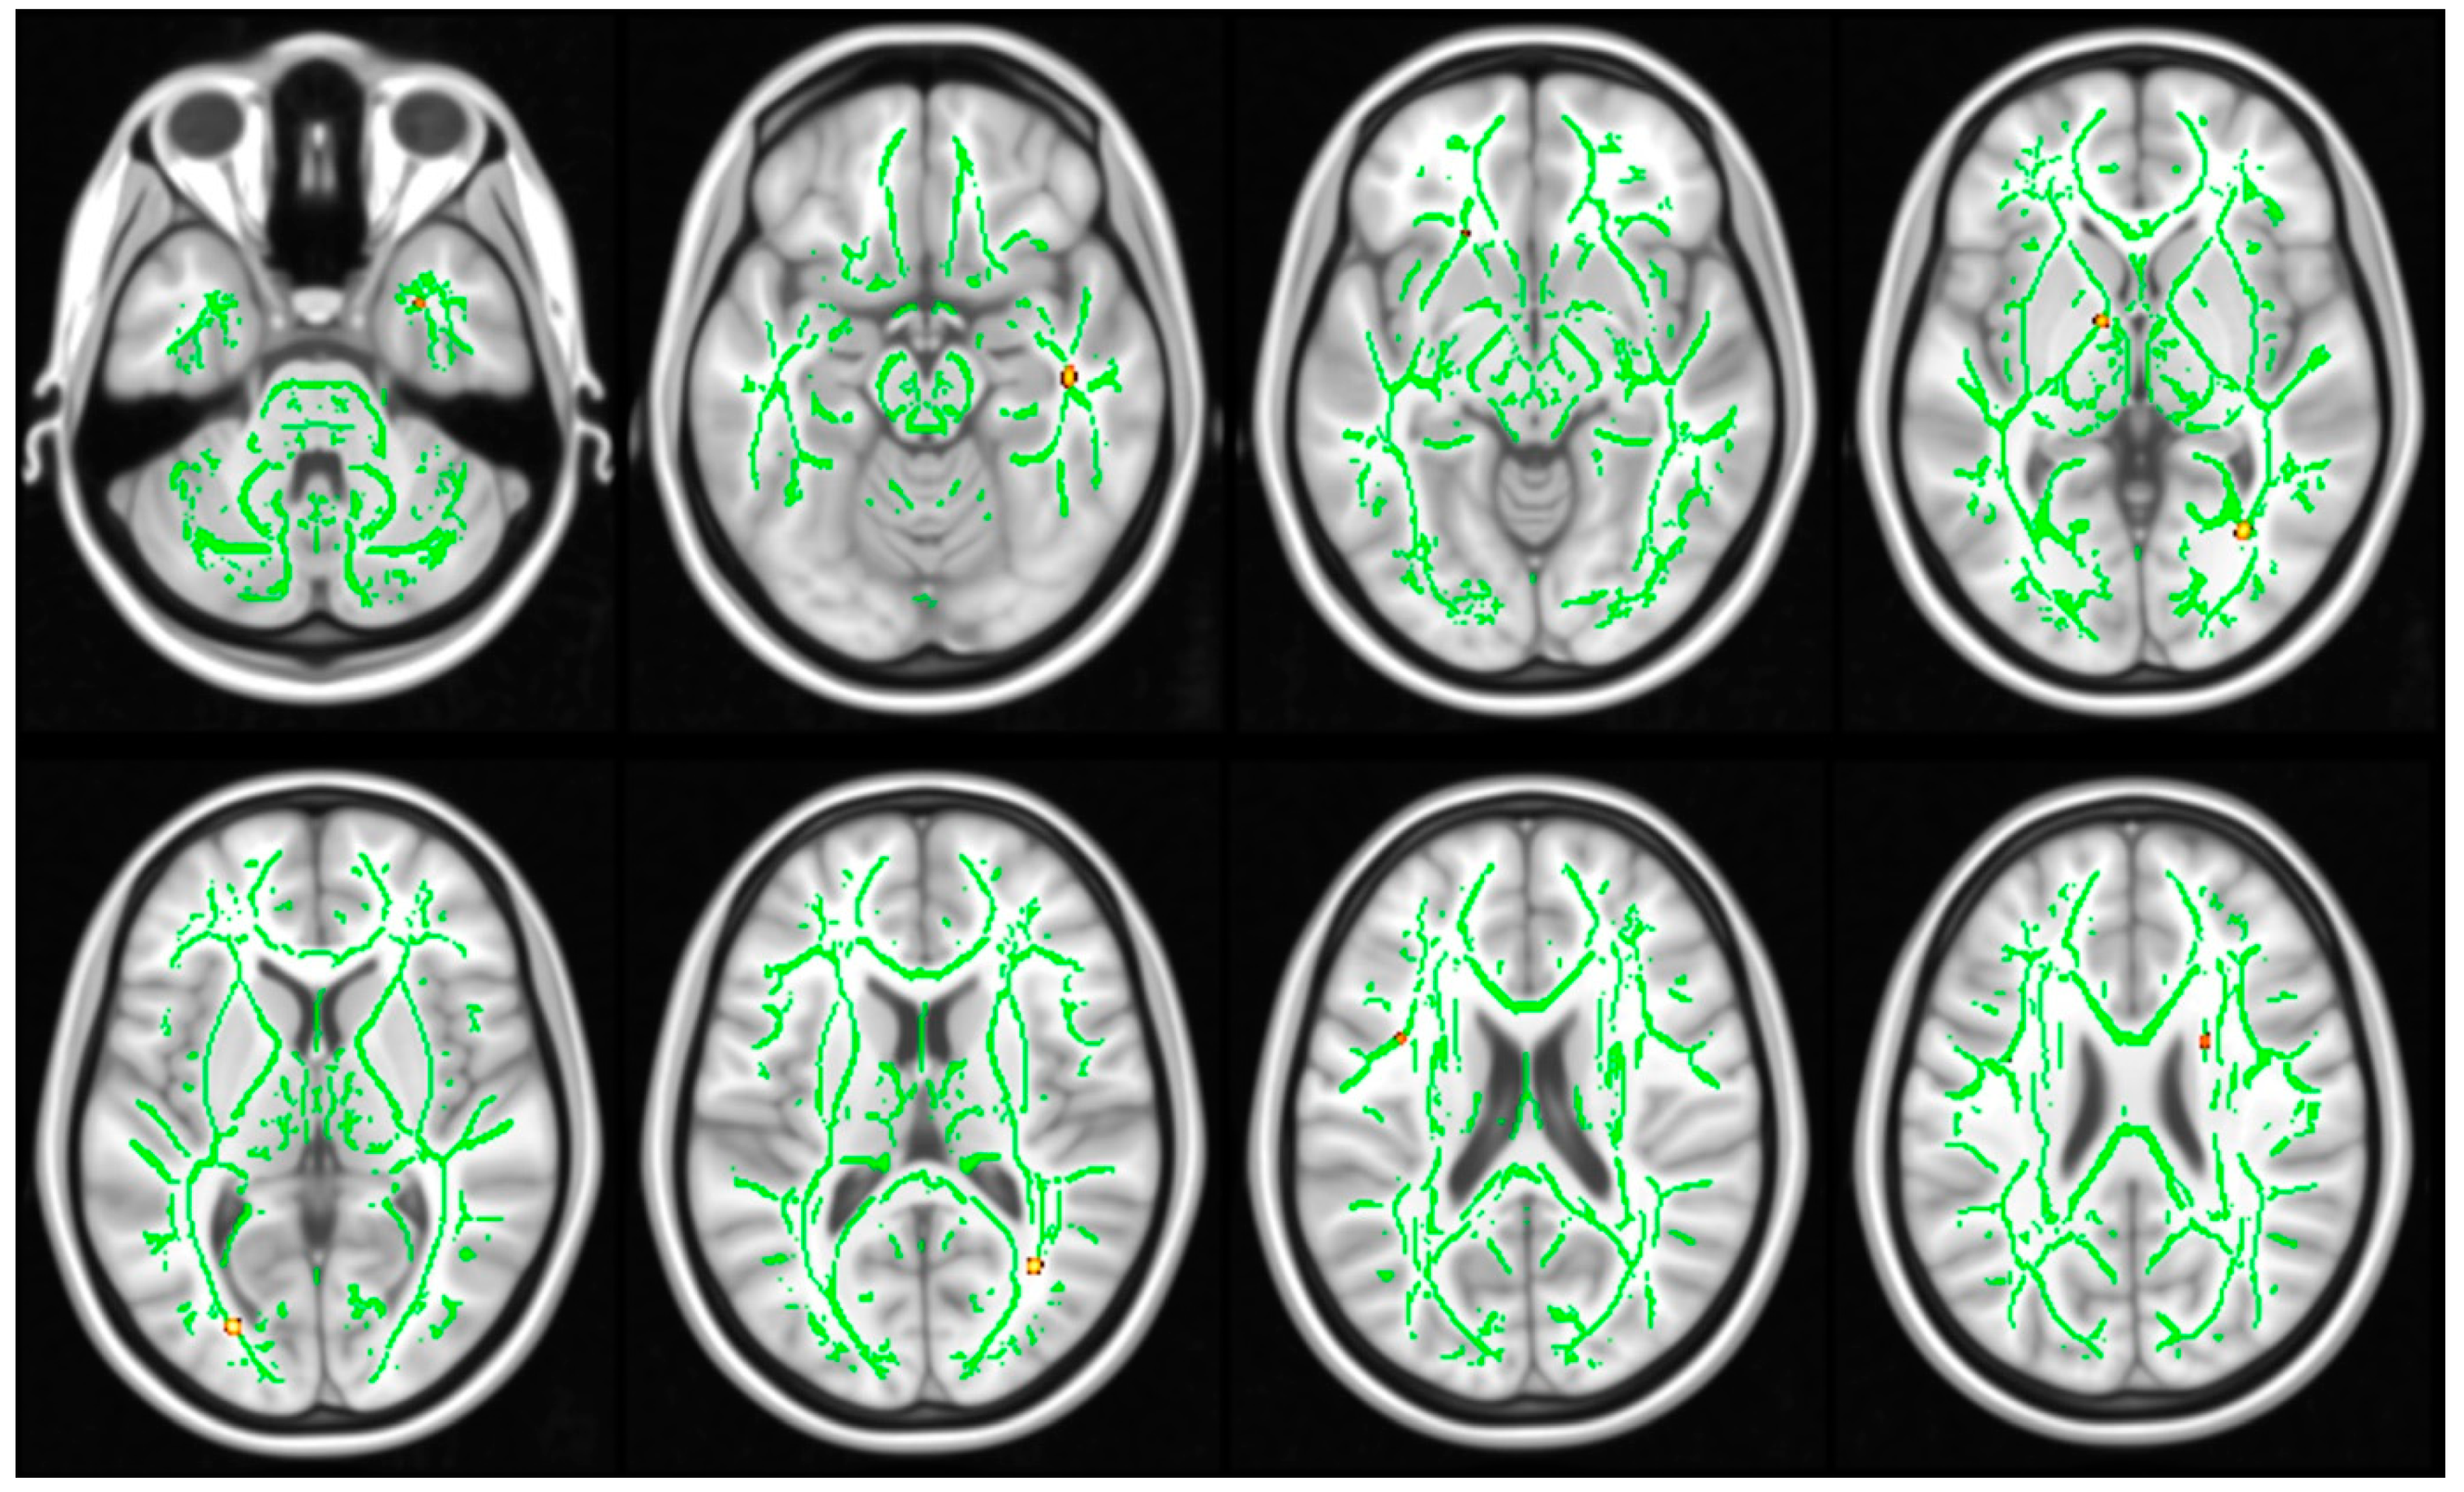

3.3. DTI Results

2.3.3. Statistical Analysis